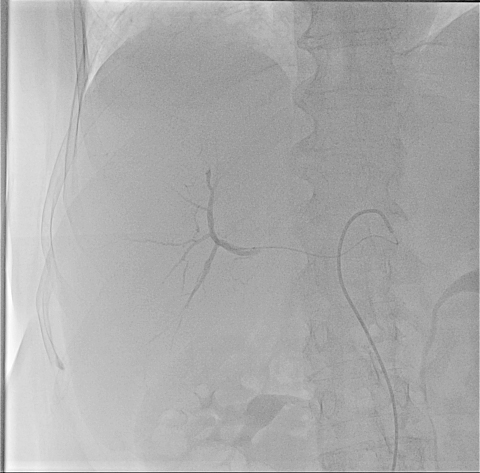

Селективная ангиография верхней брыжеечной артерии, от которой отходит собств. печеночная артерия

В мае 2014г. инвазивным кардиологом отдела ангиографии медицинского центра “Эребуни” Арсеном Цатуряном впервые была проведена операция – трансартериальная хемоэмболизация печеночной артерии, что заложило начало для дальнейшего проведения такого рода операций в стенах мц “Эребуни”.

21.03.2015г. больной И. А., у которой было злокачественное образование правой доли печени больших размеров, была проведена ангиография висцеральных артерий и селективная хемоэмболизация правой печеночной артерии с применением препаратoв Hepasphera 25 mg+Doxorubicin 100 mg.